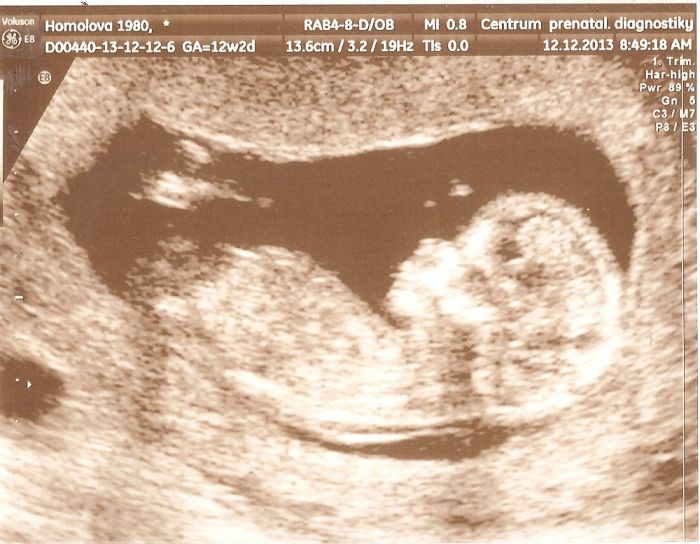

Ahojky holky, tak konečně jsem se sem dostala (je to nějaký hektický posledních pár dní

), abych se mohla pochlubit, že jsme v úterý na screeningu dopadli dobře a přikládám fotečku. Prcek byl akční a mával na nás, přikládám fotečku...akorát pohlaví nám pan doktor neřekl, že by to ještě nechal otevřený...tak uvidíme...